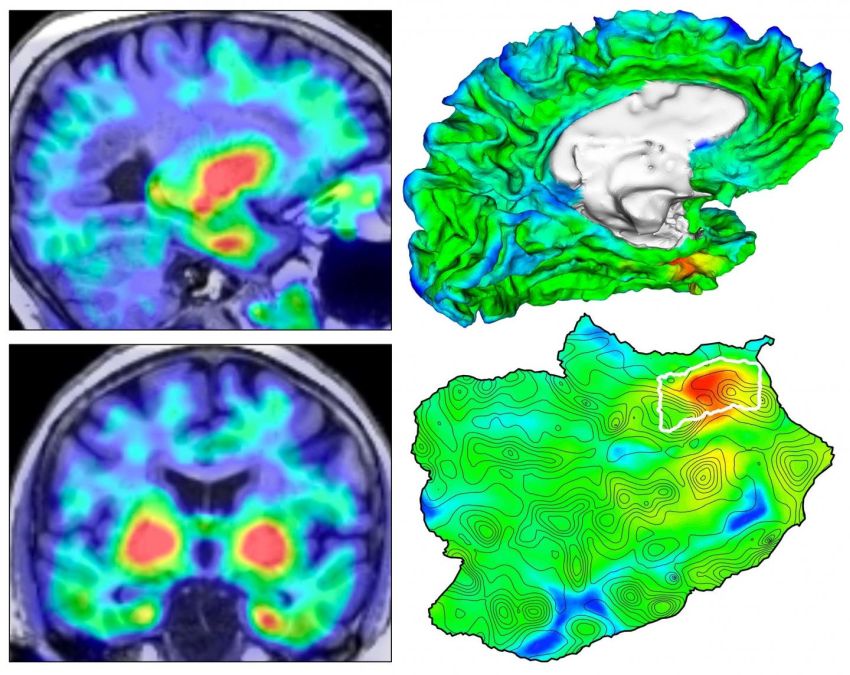

Quattro viste dell'origine della tauopatia in vivo. A sinistra, scansioni PET TAU di un soggetto cognitivamente normale; a destra in alto, superficie in 3D del cervello con sovrapposizione della pet tau; sotto, mappa piana che mostra il dettaglio topografico di anatomia superficiale con origine della tau identificata dal contorno bianco. (Fonte: J.S. Sanchez et al.)

Il metodo ha rivelato che la TAU [anomala] emerge principalmente in un'area del cervello chiamata corteccia renale, prima di diffondersi altrove, suggerendo che puntare la TAU in questa posizione potrebbe potenzialmente rallentare la progressione del MA.

Il team ha applicato la propria tecnica a 443 partecipanti adulti, inclusi 55 pazienti con MA, e ha scoperto che i depositi di TAU emergevano per la prima volta nella corteccia rinale, indipendentemente dall'amiloide-beta, prima di diffondersi alla neocorteccia temporale.

"Questi risultati suggeriscono che la corteccia rinale è un biomarcatore della diffusione della TAU a valle; si potrebbero quindi progettare studi terapeutici in cui la riduzione della diffusione della TAU sia una misura di esito", concludono gli autori.